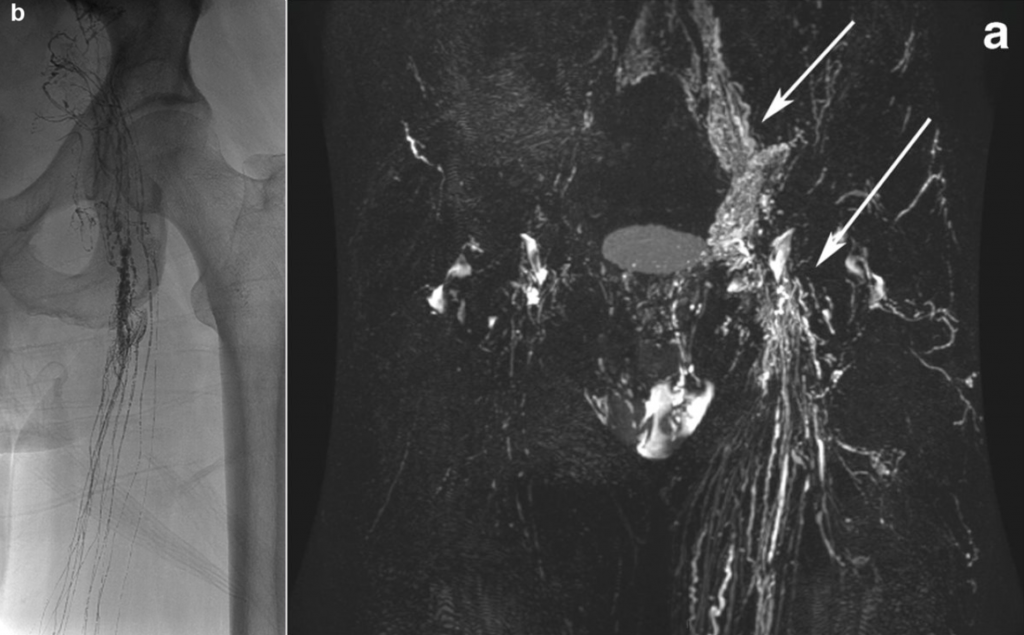

Lymphangiography

The lymphatic system plays a central role in the transport of tissue fluid, fats, and immune cells throughout the body. Disorders of this system can lead to leakage of lymph fluid (lymphatic leakage) or impaired lymph drainage. Such complications may occur, for example, after surgery, in tumor diseases, or due to congenital malformations, and may manifest as chylothorax, lymphatic fistulas, or persistent lymph collections.

Lymphangiography is a minimally invasive imaging procedure used to visualize the lymphatic system [8][9]. In this procedure, fine lymphatic vessels—usually in the region of the dorsum of the foot or the groin—are punctured, and a contrast agent is introduced into the lymphatic system. The lymphatic vessels and potential leakages can then be visualized using MRI.

In addition to its diagnostic role, lymphangiography can often be directly combined with interventional therapy. Leaking lymphatic vessels can be selectively sealed, and pathological lymphatic connections can be treated. In many cases, this allows surgical treatment to be avoided.

At the Institute of Diagnostic and Interventional Radiology, lymphangiography is used both for precise diagnosis of complex lymphatic disorders and for minimally invasive treatment of lymphatic leakages. Modern image-guided techniques enable visualization and targeted treatment of even very small lymphatic vessels.